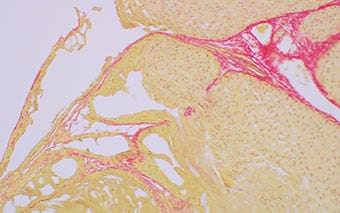

Mouse Lung Tissue (Stained with Picrosirius Red)

Brightfield observation

Figure 1: 100 W Halogen Lamp

Figure 2: BX53 microscope equipped with the high luminosity and high color rendering LED